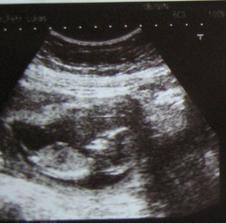

24.11. by měl přijit na svět naš Dominiček.Dnes 29.září začínáme 31.tyden a mame +6kg.Už mam vše nakoupeno ted už nas čekaji jen dodělávky na dětskem pokojíčku.Maminku pěkne kopu aby to se mnou neměla tak jednoduche a to jsem teprve v bříšku...Ale má mě moc rada a už se na mě moc moc těší dokonce má už zabaleno do porodnice.No co kdyby se mě chtělo na svět dřív. 😀.Dnes 8.října jsme byly u pana doktora tak mame zase o +3kg vic a uz jsme hlavičkou dolu.Takže jsme připravení jen aby se mu nechtělo otačet..😀 a příště jdem na ozvy...Dnes jsme byly na ozvach bylo to super a u pana doktora taky vse v poho mame +1kg.Stale rosteme 😀.Dne 12.11.jsme byly opet na kontrola vse je v poradku mame uz celkem +12kg a jsme v 38.tydnu.A je to vse za nami uz jsme 2 mama a já.Narodil jsem se v nedeli 30.11.2008 ve 14,40 a mel jsem 3,20kg a 49cm.